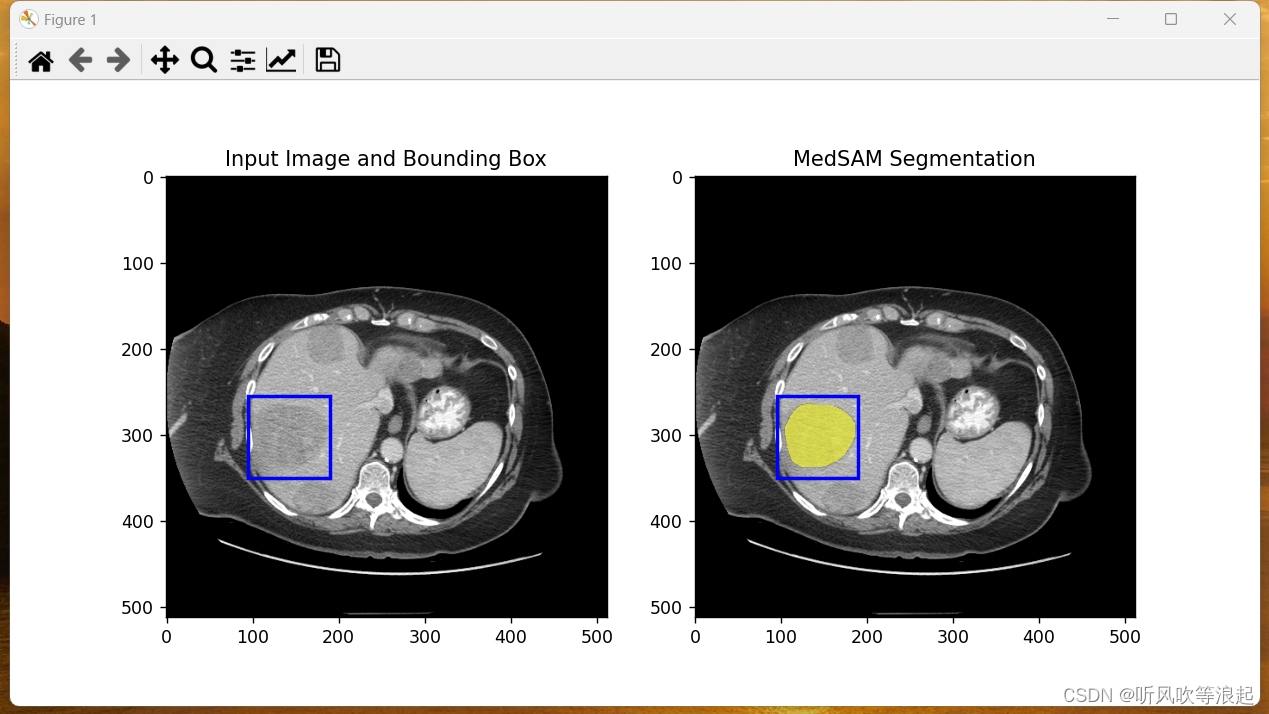

运行 MedSAM_Inference.py 脚本即可:

这里会自动推理assets下的demo图像,然后保存在这里

参数如下:

-i input_img

-o output path

--box bounding box of the segmentation target

因为SAM模型需要提示工程,所以传参的时候,也需要指定。这里是边界框,默认给定了。如果想要检测其他区域,需要更改这个bbox到自己想要推理的区域